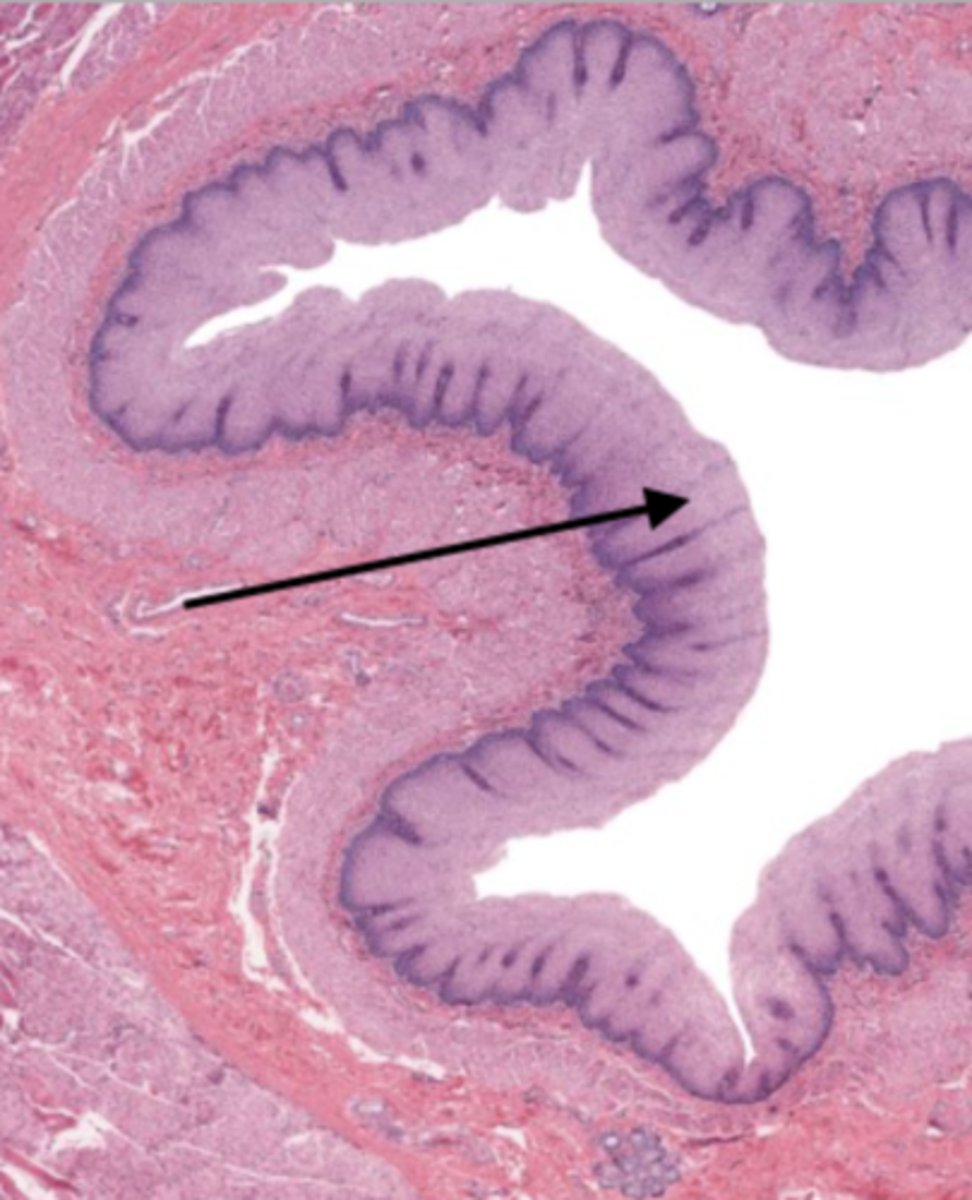

jejunum (histology)

villi (jejunum)

intestinal crypts (jejunum)

lumen (jejunum)

mucosa (jejunum)

mucosal epithelium (jejunum)

lamina propria (jejunum)

muscularis mucosa (jejunum)

submucosa (jejunum)

contains glands and blood supply

muscularis externa (jejunum)

serosa/adventitia (jejunum)